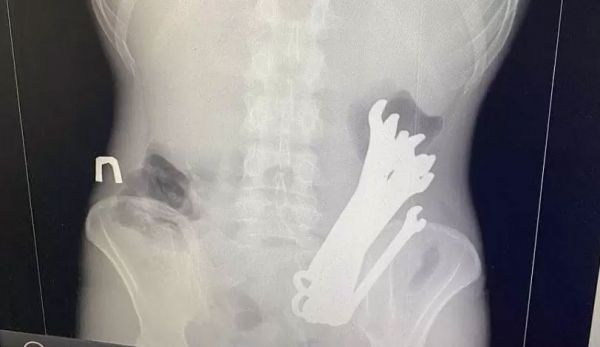

В больнице скорой медицинской помощи (БСМП) Николаева установили новое оборудование, которое повысит качество и скорость оказания медицинской помощи.Читайте НН в Telegram: только важные новостиВ арсенале врачей теперь операционный микроскоп для нейрохирургии, цифровая рентгенографическая система, биполярный резектоскоп для урологии и система для бипортальной спинальной нейрохирургии.БСМП – это ключевое медучреждение не только для Николаевской области, но и для соседней Херсонщины, поскольку здесь работает единственное на две области нейрохирургическое отделение.